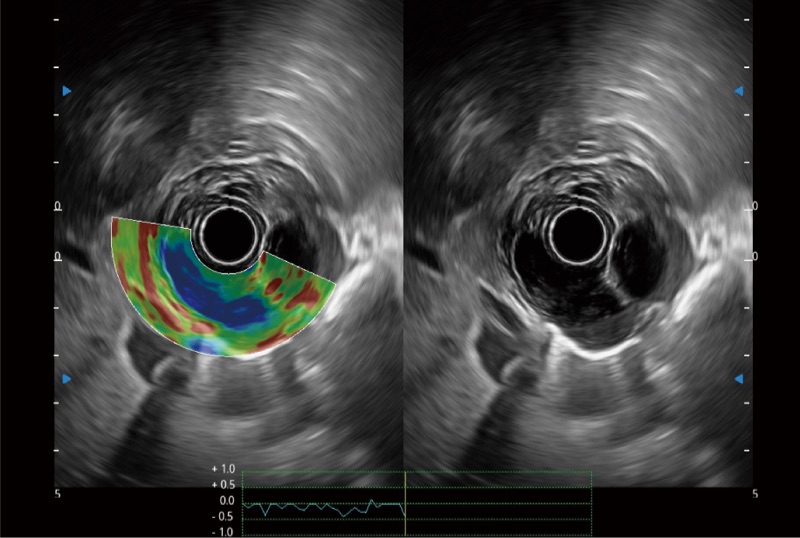

可人为将灰阶图像转变成彩色的显示方式,增强人眼对于不同回声强度的敏感度,主观上增加了图像分辨率